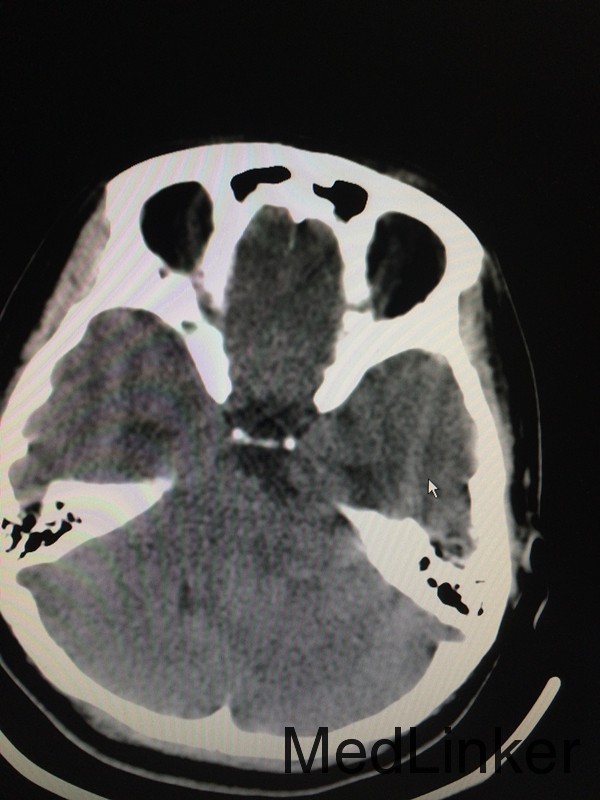

主诉:头晕头痛5月余,伴听力下降视物模糊3个月 病史:患者28岁女性,于5个月前无明显诱因出现头痛头晕,3个月前出现视物模糊,伴耳鸣,于外院行头颅MRI提示:左侧桥小脑角区占位,考虑听神经瘤。

查体:左侧轻微面瘫,左侧面部感觉稍减退,余无特殊 辅助检查:头颅CT提示左侧桥小脑角区类圆形肿物,考虑听神经瘤可能,四脑室受压变窄并右移

诊断:左侧听神经瘤 治疗:行左侧桥小脑角区占位切除术,术后病理提示左侧桥小脑角神经鞘瘤